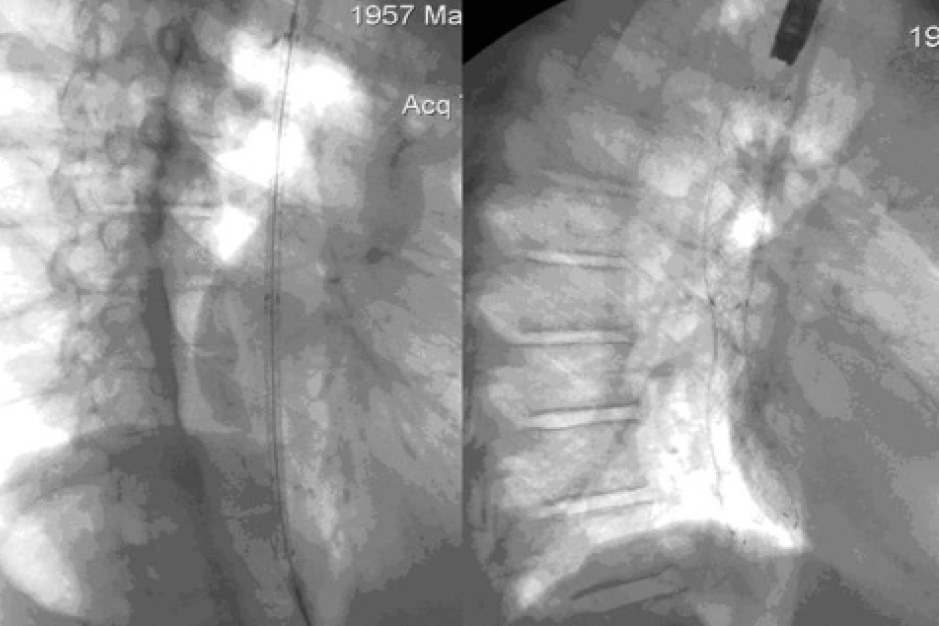

Расстояние между свищом и зоной стеноза составило 13 см, что потребовало применения самого длинного стента (максимальная длина в расправленном состоянии 20 см). На контрольном рентгенконтрастном исследовании подтекания в бронхи контраста не отмечено, зона стеноза проходима (рис. 3). Максимальное раскрытие стента происходило не сразу, а в течение нескольких суток. Поэтому динамический рентгенологический контроль является неотъемлемой частью всей методики при установке пищеводных стентов. Рентгенконтрастное исследование выполнялось сразу после окончания стентирования и далее через сутки. Также данное исследование позволяло исключить миграцию стента и перфорацию пищевода.

Рис. 3. Рентгенконтроль сразу после стентирования. Подтекания контрастного вещества за пределы стента не выявлено

Пероральный прием пищи разрешался после констатации факта полного расправления стента и отсутствии смещения по длине. Пациент мог покинуть стационар в этот же день. Первый день он мог употреблять воду и жидкую пищу, в последующие дни, консистенция и плотность продуктов расширялась. Стентирование пищевода выполняли в эндоскопическом кабинете, как правило, в утренние часы. За 10–15 минут производилась премедикация, включающая введение растворов промедола и атропина. Все вмешательства осуществлялись под внутривенной седацией. Для точной детализации успешности проведения стентирования использовались различные параметры: субъективные оценки пациентов (определение степени дисфагии и изменение качества жизни после оперативного вмешательства); параметры опухолевого стеноза, измеренные при помощи рентгенологического и эндоскопического методов; статические наблюдения за количеством осложнений (поздних и ранних); измерения продолжительности жизни пациентов.